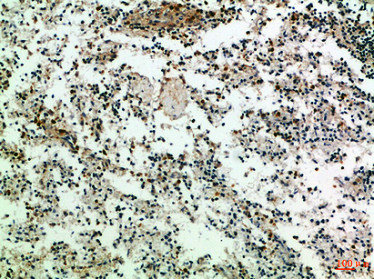

圖片:

應用范圍:IHC,ELISA

Application Recommended Dilution IHC IHC-p:1:50-300 ELISA 1:10000-20000 -

- the immunohistochemical staining patterns of CD3 and CD20 in Malignant Lymphoma Cells, were investigated. PMID: 28442514